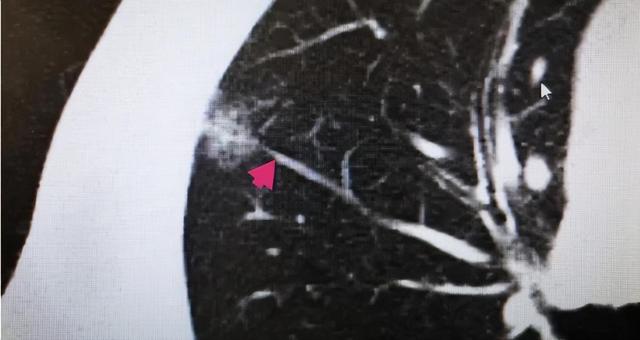

6、血管集束征:很多朋友对这个名字比较陌生 , 但是换一个名字应该就明白了 , 即血管穿行 , 是指结节与血管相连 , 且血管常有增粗或扭曲等形变;发现有血管穿行要引起重视 , 但是应与结节后血管水平穿行做区别;